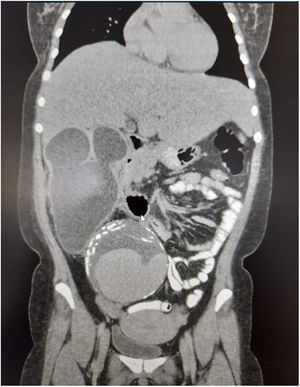

Caso clínicoPaciente mujer de 38 años de edad, quien acude al servicio de urgencias de un hospital de nivel III de complejidad, por dolor abdominal en el hipocondrio derecho, tipo cólico, sin irradiación, en la escala subjetiva del dolor 6/10, asociado a leve ictericia en escleras, náuseas y emesis en 3 ocasiones hace 4 días. No refiere otros síntomas. En el historial médico sin antecedentes destacados. Al examen físico con signos vitales estables (presión arterial: 110/70mmHg, frecuencia cardiaca: 78 latidos/minuto, frecuencia respiratoria: 16 respiraciones/minuto, saturación de oxígeno: 90%, temperatura: 37°C). A nivel cefálico; leve ictericia en esclerótica, y en el abdomen; dolor en hipocondrio derecho a la palpación superficial y profunda, sin irradiación, signo de Murphy positivo y masa en hipogastrio, pulsátil, no dolorosa, sin signos de irritación peritoneal, sin signos de respuesta inflamatoria sistémica. El resto del examen físico fue negativo para otros hallazgos. Los análisis de sangre muestran leucocitosis, función hepática y renal alterada y bilirrubina elevada (tabla 1). Ante este escenario por masa en hipogastrio, se solicita ecografía de abdomen completo, iniciando líquidos por deshidratación moderada y vigilancia clínica. La ecografía abdominal reveló una bolsa hidronefrótica derecha y una masa heterogénea en fosa iliaca derecha mal delimitada, por lo que se decidió realizar una tomografía axial computarizada (TAC) para determinar la naturaleza de la masa (fig. 1). La TAC muestra dilatación aneurismática que compromete la arteria iliaca común derecha con un trombo mural excéntrico y calcificaciones en su pared (fig. 2). Se valora por cirugía vascular que considera arteriografía de los vasos abdominales para establecer la anatomía del aneurisma. Se procede a realizar la intervención quirúrgica, en los hallazgos intraoperatorios se observa un aneurisma gigante de 10cm en la arteria iliaca común derecha con proceso inflamatorio retroperitoneal, asociado a riñón atrófico, múltiples quistes con líquido turbio en cavidad peritoneal del cual se tomaron muestras para Gram y cultivo. El servicio de urología decidió realizar una nefrectomía derecha amplia con ligadura del uréter severamente dilatado, se presume que el tamaño del aneurisma provocó la hidronefrosis severa. Se realiza un lavado peritoneal abundante de la cavidad contaminada hasta drenar líquido claro. En el mismo tiempo operatorio, cirugía vascular realiza resección del aneurisma preservando la bifurcación hipogástrica, con reparación por injerto aortofemoral autólogo con endarterectomía, ligadura u obliteración de la zona iliaca, más disección de los vasos retroperitoneales, rafia de la vena cava a nivel de las venas lumbares dilatadas, ligadura de múltiples vasos intraabdominales. Además, para la extracción del injerto de la vena safena mayor se ejecuta ligadura de vasos arteriales y venosos suprarrotulianos del lado derecho con disección de la vena femoral. El injerto fue impregnado con antibiótico por desajuste de los vasos nativos.